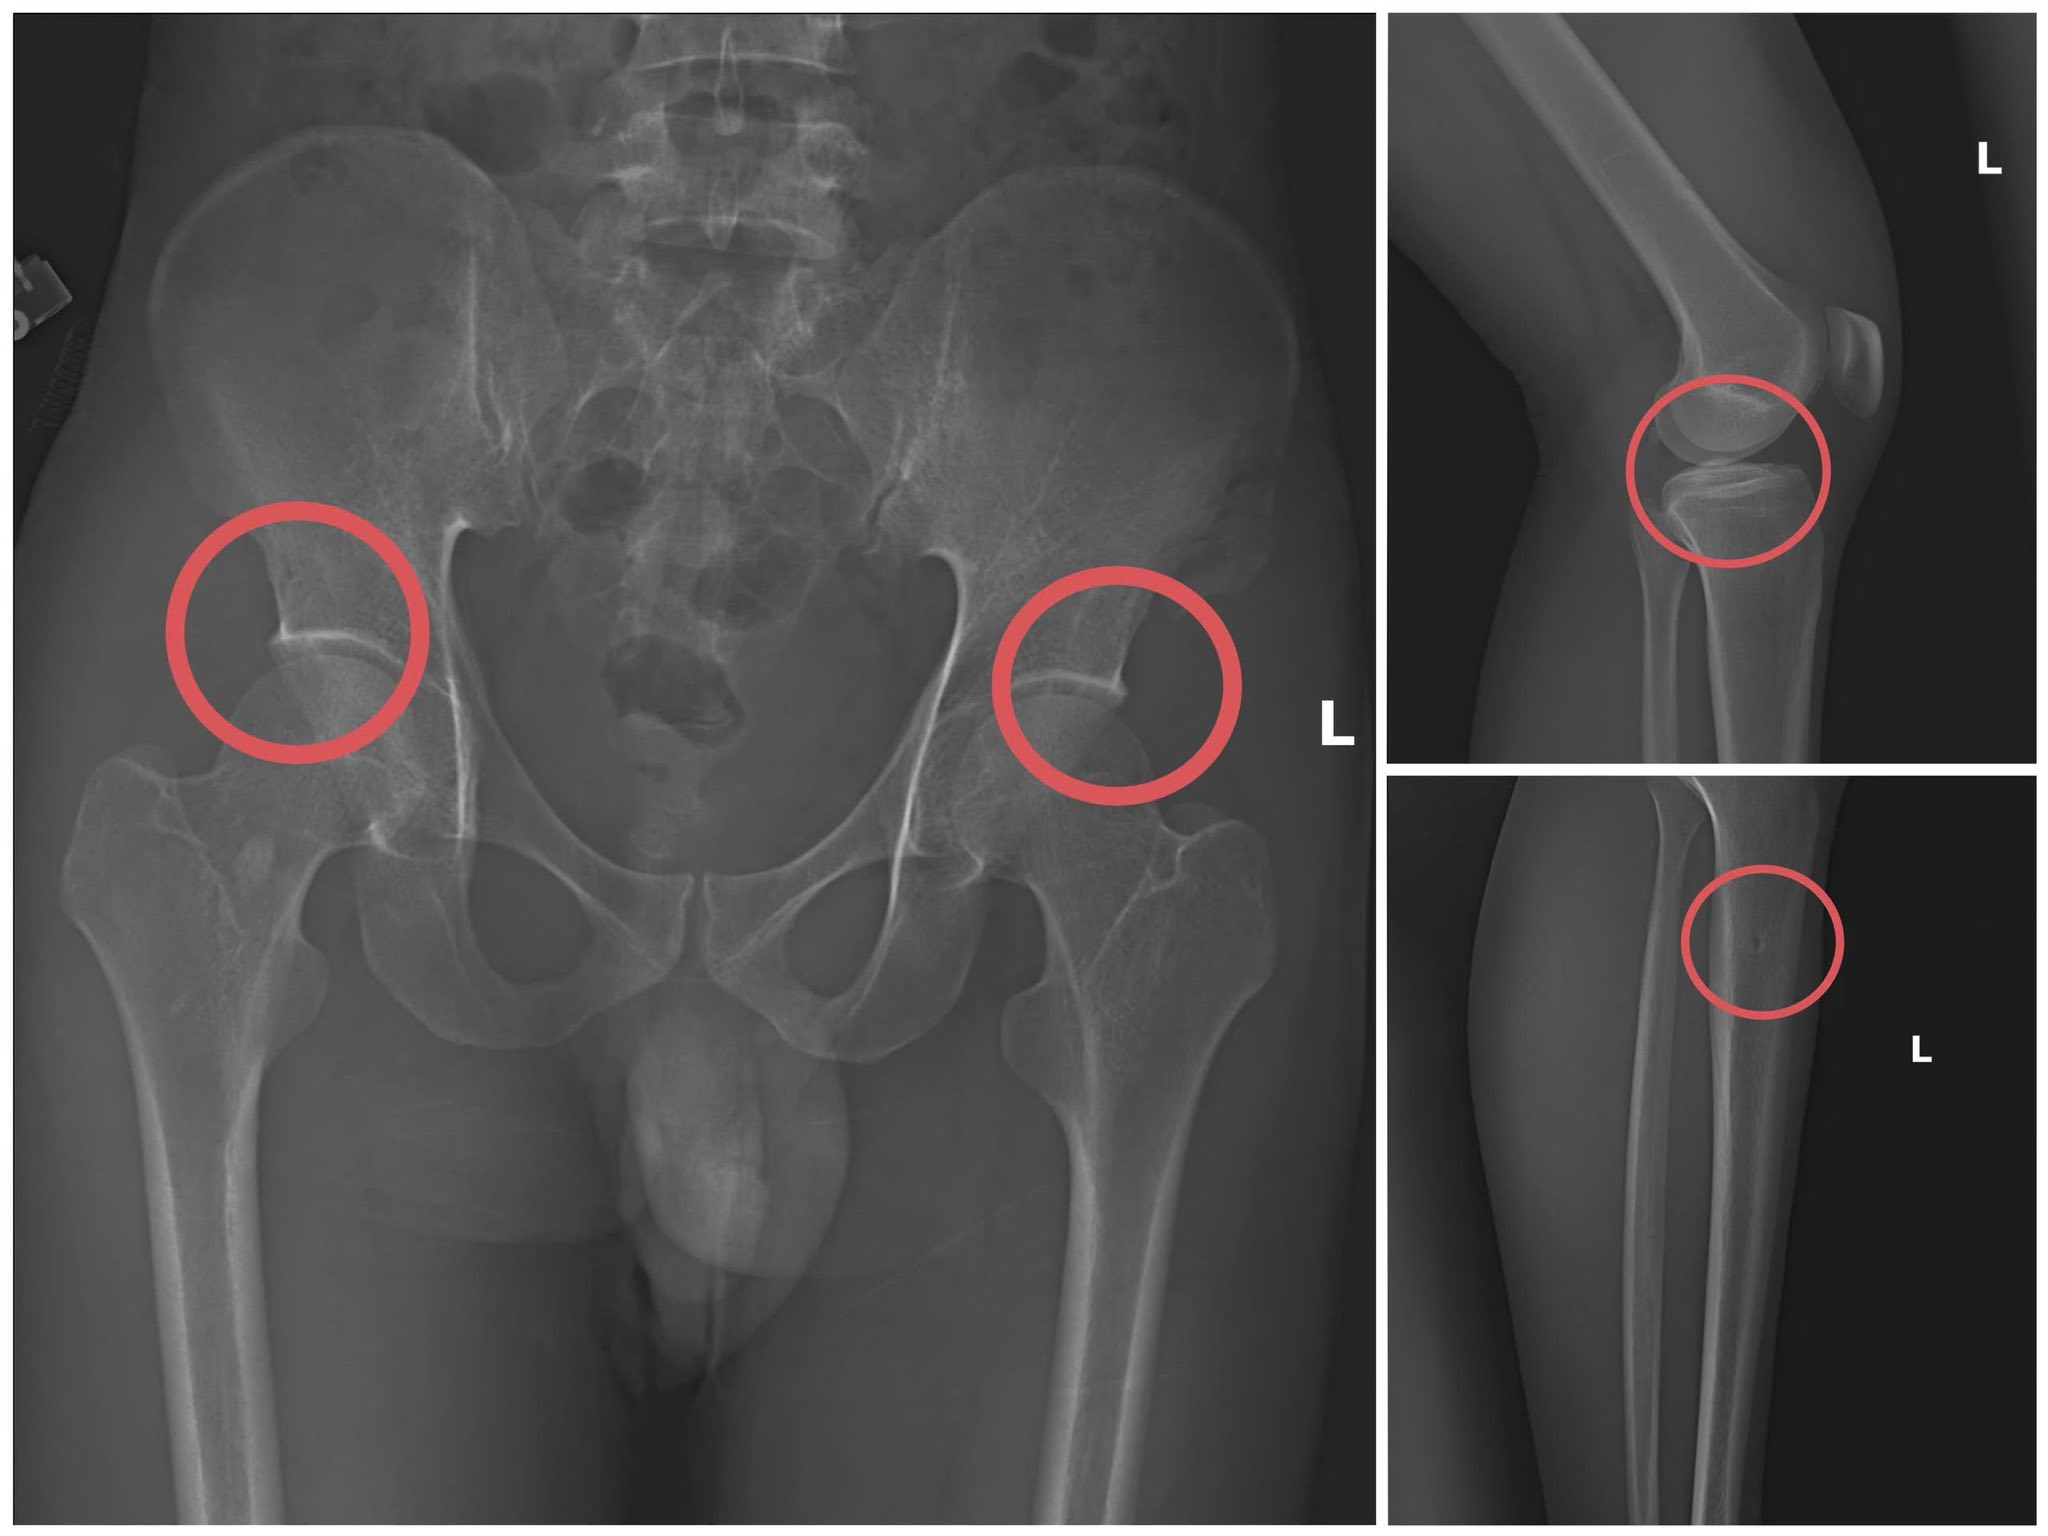

Theo thông tin từ cơ quan công an, lợi dụng thời gian dài công tác trong ngành y và am hiểu sâu cấu tạo xương - khớp, cũng như cơ chế chi trả bảo hiểm đối với các thương tích gãy xương giá trị cao, Châu dựng lên một quy trình trục lợi bài bản, từ việc vận động mua bảo hiểm, tổ chức gây thương tích, đến hợp thức hóa hồ sơ bệnh án để chiếm đoạt tiền của các công ty bảo hiểm.

Bản phim chụp XQ một số tổn thương xương do đối tượng tạo ra

Đáng chú ý, Châu trực tiếp thực hiện hành vi tiêm thuốc mê rồi dùng kim tiêm, búa đinh để tác động vào xương người mua bảo hiểm, tạo nên các vết nứt, vỡ xương tương tự các vụ tai nạn thật.

Lãnh đạo Công an tỉnh Phú Thọ đánh giá, thủ đoạn của Châu vừa tàn nhẫn, vô nhân tính, coi thường sức khỏe, tính mạng của người tham gia, vừa được tính toán kỹ để gây thương tích đúng vị trí có mức chi trả cao, khiến các công ty bảo hiểm khó phát hiện dấu hiệu gian dối.